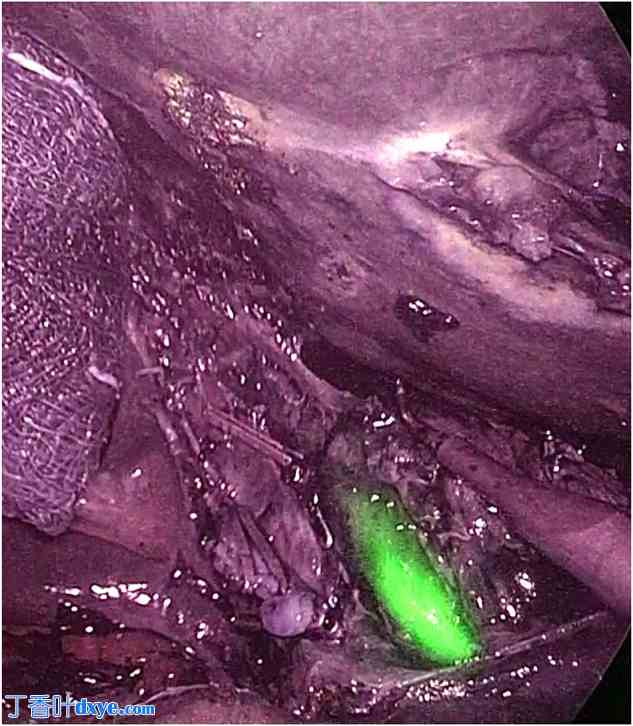

为了增强胰腺的可视性,同时最大限度地减少周围组织的干扰,Asbun 等人建议使用持续 ICG 输注。对于远端胰腺肿瘤,通常在开腹手术后立即注射;对于胰头手术,通常在胆管切除后立即注射,ICG 的输注速度为每分钟 0.4 滴。他们通过一段视频展示了该技术在胰腺十二指肠切除术中用于有胰腺炎病史的患者进行钩突解剖的实用性(图 1)。

图 1.

ICG 注射后不同时间的胰腺钩突及邻近血管。(A) 静脉 ICG 注射前,持续输注。(B) 动脉期,注射后 10 秒。注意肠系膜上动脉分支到胰腺的荧光增强。 (C) 静脉期,推注后 40 秒。肠系膜上静脉呈高荧光。ICG,吲哚菁绿;IV,静脉注射。图片由 Abun 等人提供